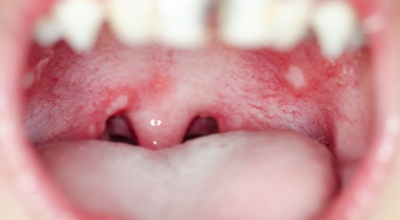

4. 구내염 원인 - 바이러스성 구내염

바이러스로 인해 나타나는 구내염도 있답니다. 단순 헤르페스 바이러스의 감염 원인인 '헤르페스성 구내염'은 주로 타액 과 같은 접촉으로 인해서 감염되어요. 또 곰팡이의 일종인 칸디다균은 원래 입안에 존재하는 상재균의 한 개지만, 만에 하나라도 면역력이 저하되면 증식해서 '칸디다성 구내염'을 병이 발생하게 됩니다.

바이러스성 구내염에 많이 관찰되는 다발성 구내염은 입 점막에 많은 소수포가 형성되어 찢어져 붕괴를 발생시킬 수이 있고 발열이나 강한 통증이 수반될 수 있습니다.